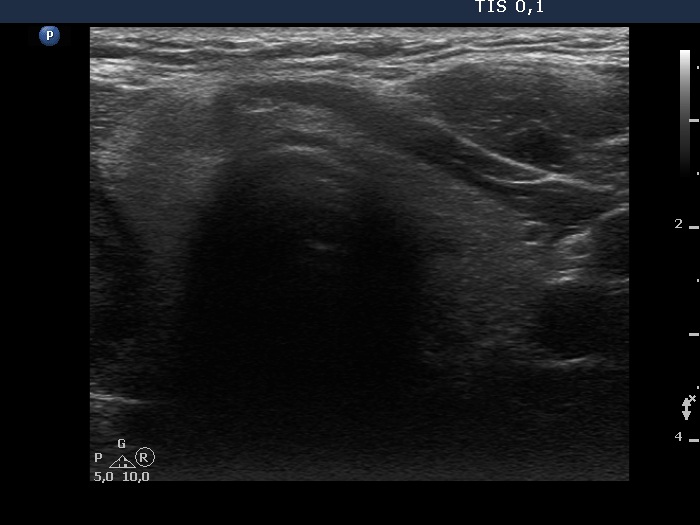

Ultrasonography. The thyroid was echonormal. There was a hypoechoic nodule in the right lobe. The dimensions of the nodule were 39x21x42 mm, width, depth and length, respectively. The lesion had a partial halo and both perinodular and intranodular vascularity.

Considering the ultrasound presentation, we gave a combined sono-cytological diagnosis of suspicion of follicular tumor.

1. On the ultrasound presentation, the likelihood of follicular tumor is around 90%.

3. In a large solitary nodule presenting either halo or perinodular vascularity, the likelihood of a follicular tumor is greater than 90%.